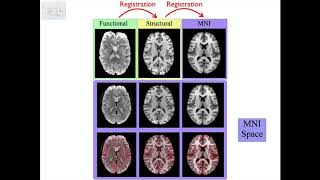

Registration: Image Registration and Distortion Correction

2. Registration: Image Spaces and Spatial Transformations

4. Registration: Single Stage and Multi-Stage Applications